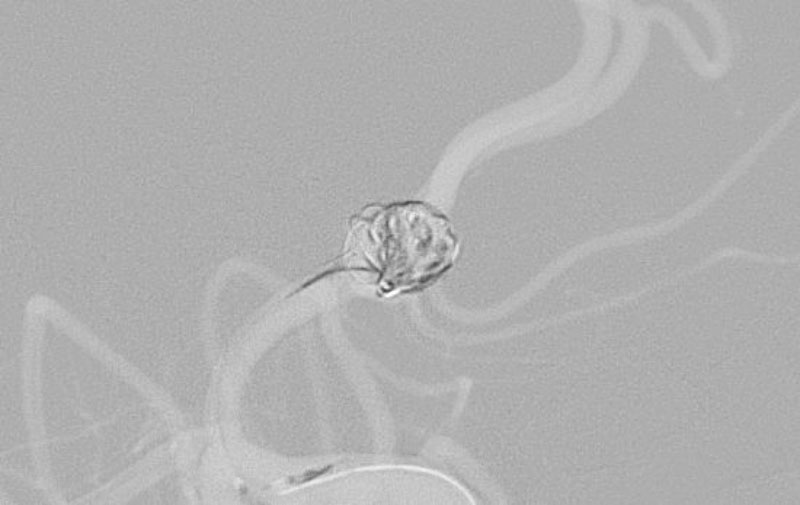

'26年4月

前交通動脈瘤

50代

大阪府の病院

No.1627 手術中